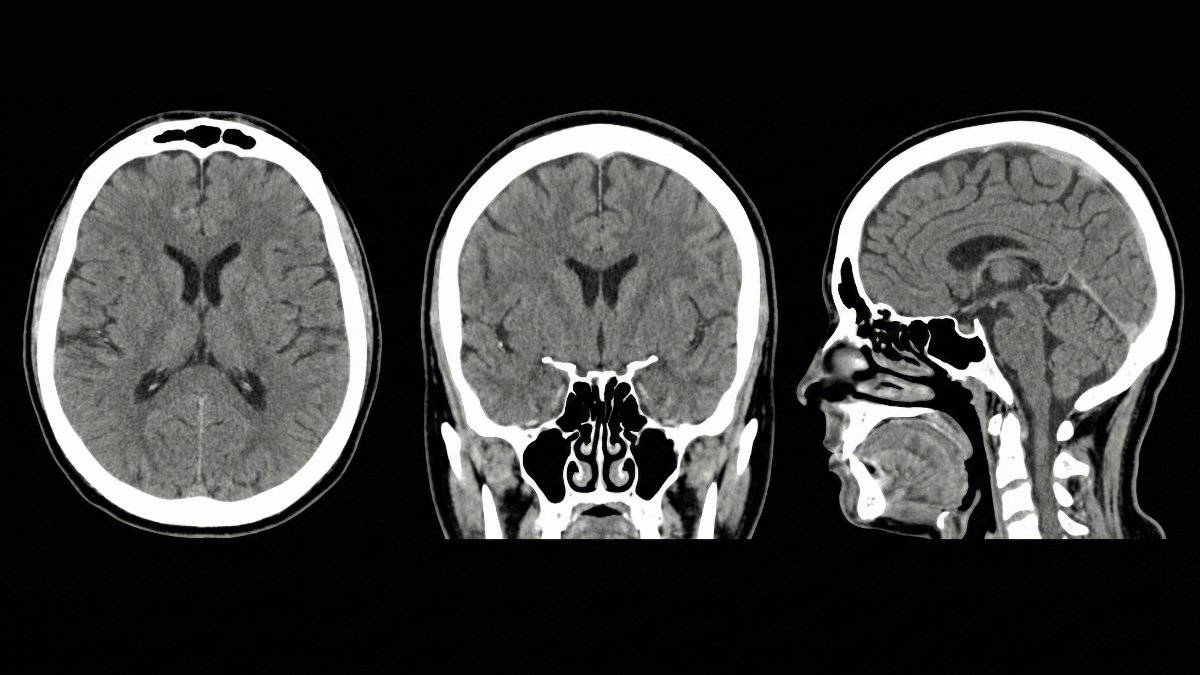

The two main toxins are amyloid-beta and tau. These proteins clump together in Alzheimer’s patients. Your glymphatic system should wash them away every night. But when it fails, they stick around and damage brain cells.

A January 2026 study tested 39 people. After normal sleep, their brains cleared these proteins. After sleep deprivation, the proteins stayed put. The UK Biobank tracked 40,000 adults. Those with poor cerebrospinal fluid movement had higher dementia risk.

Research shows side sleeping beats sleeping on your back or stomach. Scientists tested different positions. Lateral sleeping (on your side) moved waste out fastest. Your brain’s interstitial space actually expands during sleep. This gives the cleaning fluid more room to work.

Deep sleep matters most. A January 2025 study in Cell found that norepinephrine oscillations predict how much cleaning happens. These happen during NREM sleep. That’s the deep, dreamless kind. You need to reach this stage for maximum waste clearance.